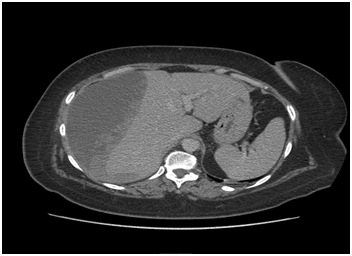

A 45 years-old woman was admitted to our hospital with right upper abdominal discomfort. She had undergone cholecystectomy a few years before and the laboratory findings evidenced: GOT 30 UI/l (n.v.<37),GPT 78UI/l(n.v.<40), gammaglutamyltranferase, GGT 330 UI/l (n.v. 537), alkalinephosphatase 220 UI/l (n.v. 53-128), total bilirubine 0.6 mg/dl (n.v. 0.2-1.2), RBC 4.64 106u/L (nv 4.40-5.60),Hb 11.9g/dl (n.v. 12.8-16.5), HCT 36.6 % (n.v. 40-50), WBC 7.64 193u/L, PT 107% ( n.v. 70-130), PT INR 0.95 (n.v. 0.90-1.30),PTT 30.0 sec(26.0 40.0), amylase 64, lipase normal value. Good general conditions with clinical history of hernia lumbar with NSAIDs irregular treatment and epilepsy in effective drug treatment. She was use of analgesics for headache. Indication for ERCP was placed for detection of biliary sludges in common bile duct (CBD) without dilatation of extrahepatic and intrahepatic bile ducts. Sphincterectomy was performed over a hydrophilic guide, without immediate complications with clearance of sludges from common bile duct by Dormia basket (Figure 1). Two hours later she developed severe right upper abdominal pain not being susceptible to common analgesics. She was not hyperpiretic with normal laboratory tests and no free air to Rx-ray abdomen carried out after about 4 hours of the procedure. There was no signs of peritoneal involvement to clinic examination. Since the abdominal persisted with a drop of 2.5 grams of haemoglobin, RBC 3.67 and HCT 29.5, WBC 12.08, amylase 57,GOT 57,GPT 130, GGT 213,alkaline phosphatase 178 and total bilirubin 0.5, a CT abdomen was performed. It highlighted a wide collection heterogeneously hypo-isodense with densitometric values of fluid type blood in the subcapsular right liver, between the posterior and anterior-medial area, without signs of active bleeding or capsular leak. No hemoperitoneum, no pneumoperitoneum, no dilated the intra and extrahepatic bile ducts (Figure 2). Large pleural effusion with hypoventilation lower lobe and posterior segment of right upper lobe (Figure 3). The patient still presented without fever with abdominal pain attenuation. On the surgeon input, conservative management was performed with intravenous fluid replacement and broad-spectrum antibiotics. After five days she presented fever and abdominal CT was unchanged from the previous control, except relief of subcapsular tiny gas bubbles. On this relation and the pulmonary compromission, she was under surgical treatment for hematoma and pleural effusion drainage. At surgery it was a massive subcapsular hematoma, partially coagulated, which covered the entire liver right and partially the fourth segment with intimate adherence to the diaphragm and lateral shower right. Pleural effusion was clear without bacterial infection. She was symptoms free with excellent postoperative course and was discharged after about 10 days after surgery with normality at laboratory parameters and abdominal ultrasound scan. Serial ultrasonographic and rx-ray examinations were performed with complete resolution of pleural effusion and pulmonary ventilation with persistently normal liver morphology at the end of 30th day. She remained asymptomatic at subsequent follow up.

Figure 2 CT scan of upper abdomen showing the subcapsular hematoma of the right lobe of liver.